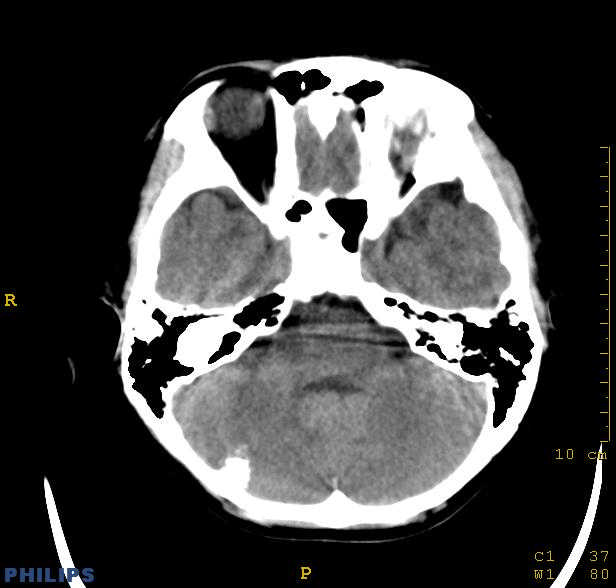

标题: PED0043:头颅平扫 男12岁.典型结节性硬化 [打印本页]

标题: PED0043:头颅平扫 男12岁.典型结节性硬化

典型结节性硬化

[病因病理]

结节硬化是常染色体显性遗传缺陷或基因突变引起的疾病,脑部病理可见神经胶质增生性硬化结节,位于大脑皮质、基底核及侧脑室壁的室管膜下。结节质地较硬,多有钙化。室管膜下结节可演变为巨细胞星形细胞瘤,亦可发生皮质错构瘤,常合并有其他器官畸形和肿瘤。

[临床表现]

儿童多见,在许多器官中有错构瘤生长,以皮肤、神经系统受累为主。典型临床表现为面部皮脂腺瘤、癫痫发作及智力低下。

[影像学表现]

1.ct表现:

①室管膜下有多发性小结节状钙化影,也可为单发、不强化;小结节亦可未钙化;突入脑室可以强化;但有钙化者居多,颅内异常钙化高达90%。一般出生后2年即呈典型钙化。